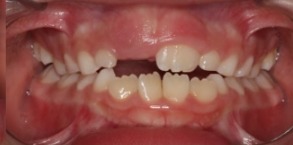

O tratamento que tem como objetivo tratar a má-oclusão através de recursos terapêuticos (aparelhos removíveis) que utilizam estímulos funcionais precocemente através de orientação mastigatória, desgaste seletivo, acréscimo às superfícies dentárias.